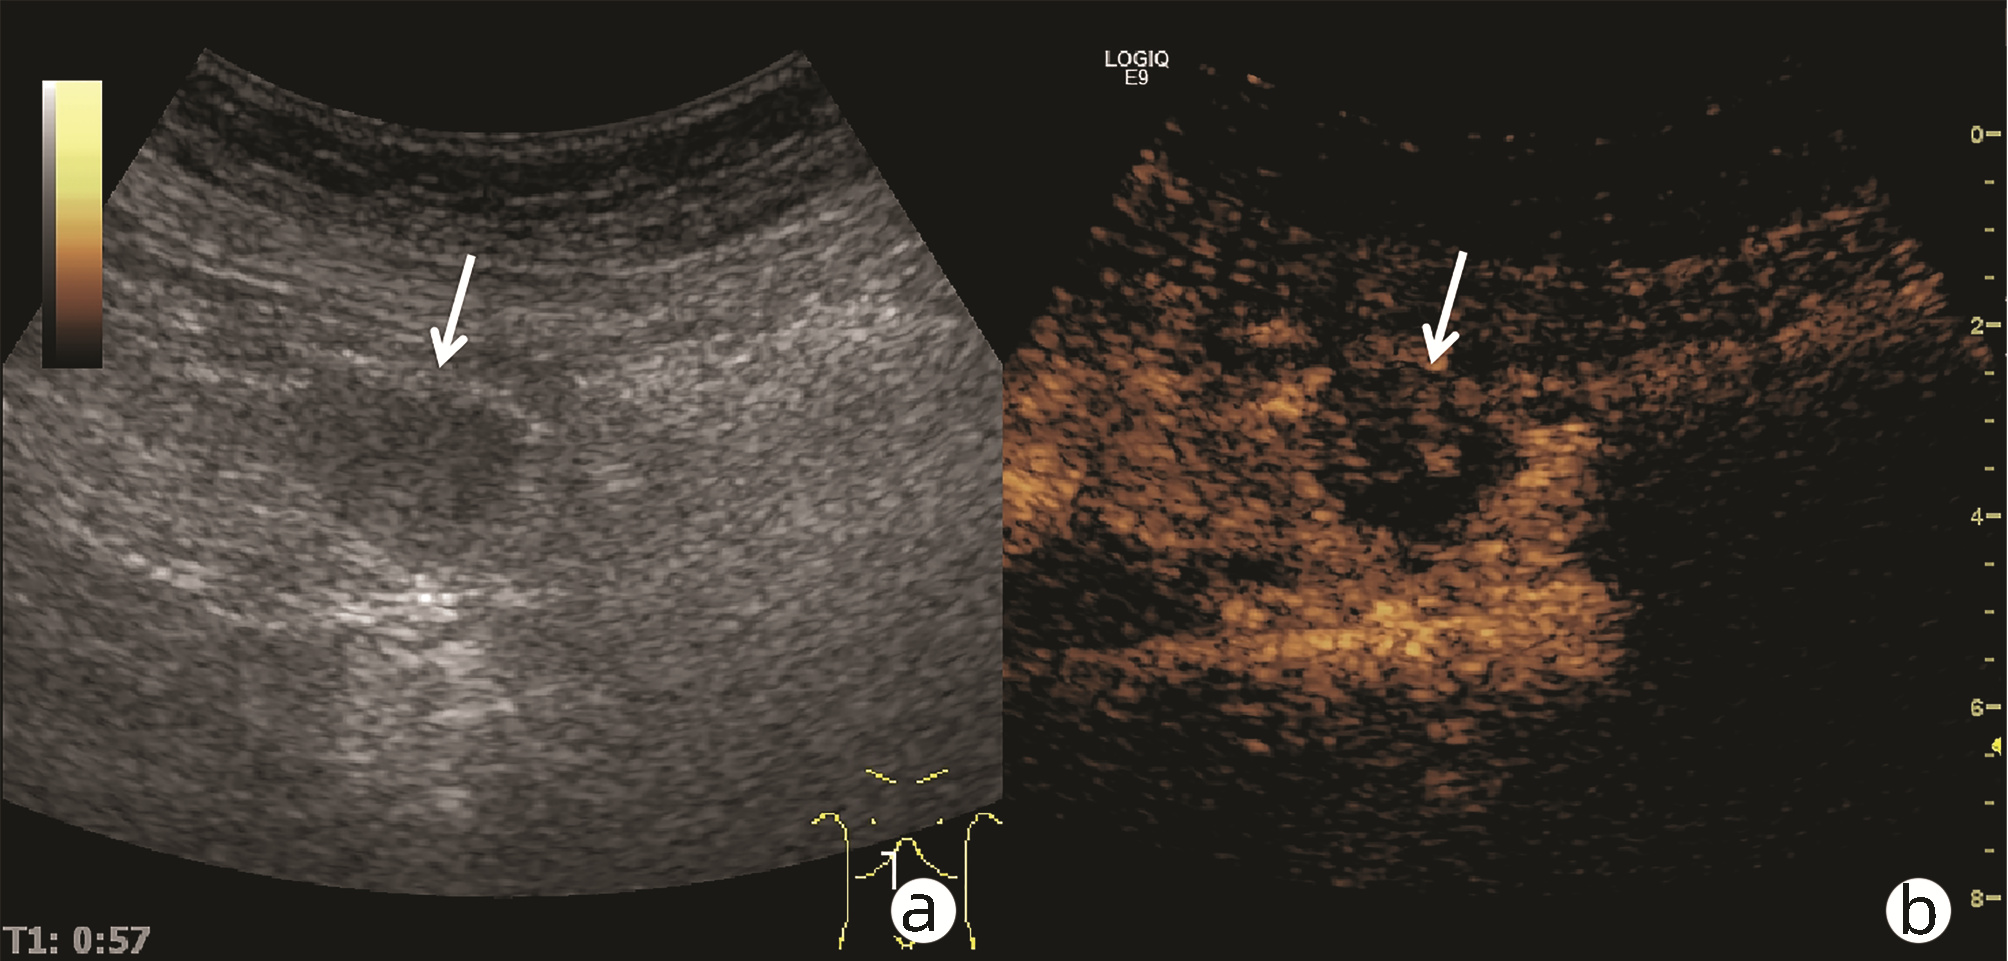

肿块型自身免疫性胰腺炎与胰腺导管腺癌的超声及超声造影表现分析

欧阳向柳, 韩云霞, 郑立春, 赵英春, 申新宇, 张文军, 王艳滨

2022, 38(6): 1351-1355. DOI: 10.3969/j.issn.1001-5256.2022.06.025

摘要(1431) HTML (553) PDF (3738KB)(51)

摘要:

目的  探讨超声及超声造影对肿块型自身免疫性胰腺炎(AIP)与胰腺导管腺癌(PDAC)的鉴别诊断价值。  方法  回顾性分析2015年1月—2020年12月唐山市工人医院确诊的11例肿块型AIP患者的临床资料及常规超声、超声造影资料,分析其特征性表现,并与23例PDAC患者的资料进行对比,计数资料两组间比较采用χ2检验。  结果  11例肿块型AIP超声造影的诊断准确性为63.64%,均为单发病灶,且均低回声,在边界清晰、形态规则、胰管扩张或截断、血流信号方面所占比例分别为54.55%、63.64%、18.18%、36.36%,而PDCA组分别为30.43%、34.78%、78.26%、21.74%,两组间是否伴胰管扩张或截断方面存在统计学差异(χ2=11.089,P<0.05),其余指标均无明显统计学差异(P值均>0.05)。超声造影中7例(63.64%)肿块型AIP动脉期呈高增强,4例(36.36%)呈等增强,静脉期5例(45.45%)呈高增强、6例(54.55%)呈等增强;23例PDAC中22例(95.65%)病灶在动脉期及静脉期均呈低增强,两者动、静脉期强化方式差异均有统计学意义(χ2值分别为30.345、30.084,P值均<0.05)。  结论  超声造影检查增强模式及是否伴胰管扩张或截断方面在肿块型AIP与PDCA的鉴别诊断中具有较高的价值。